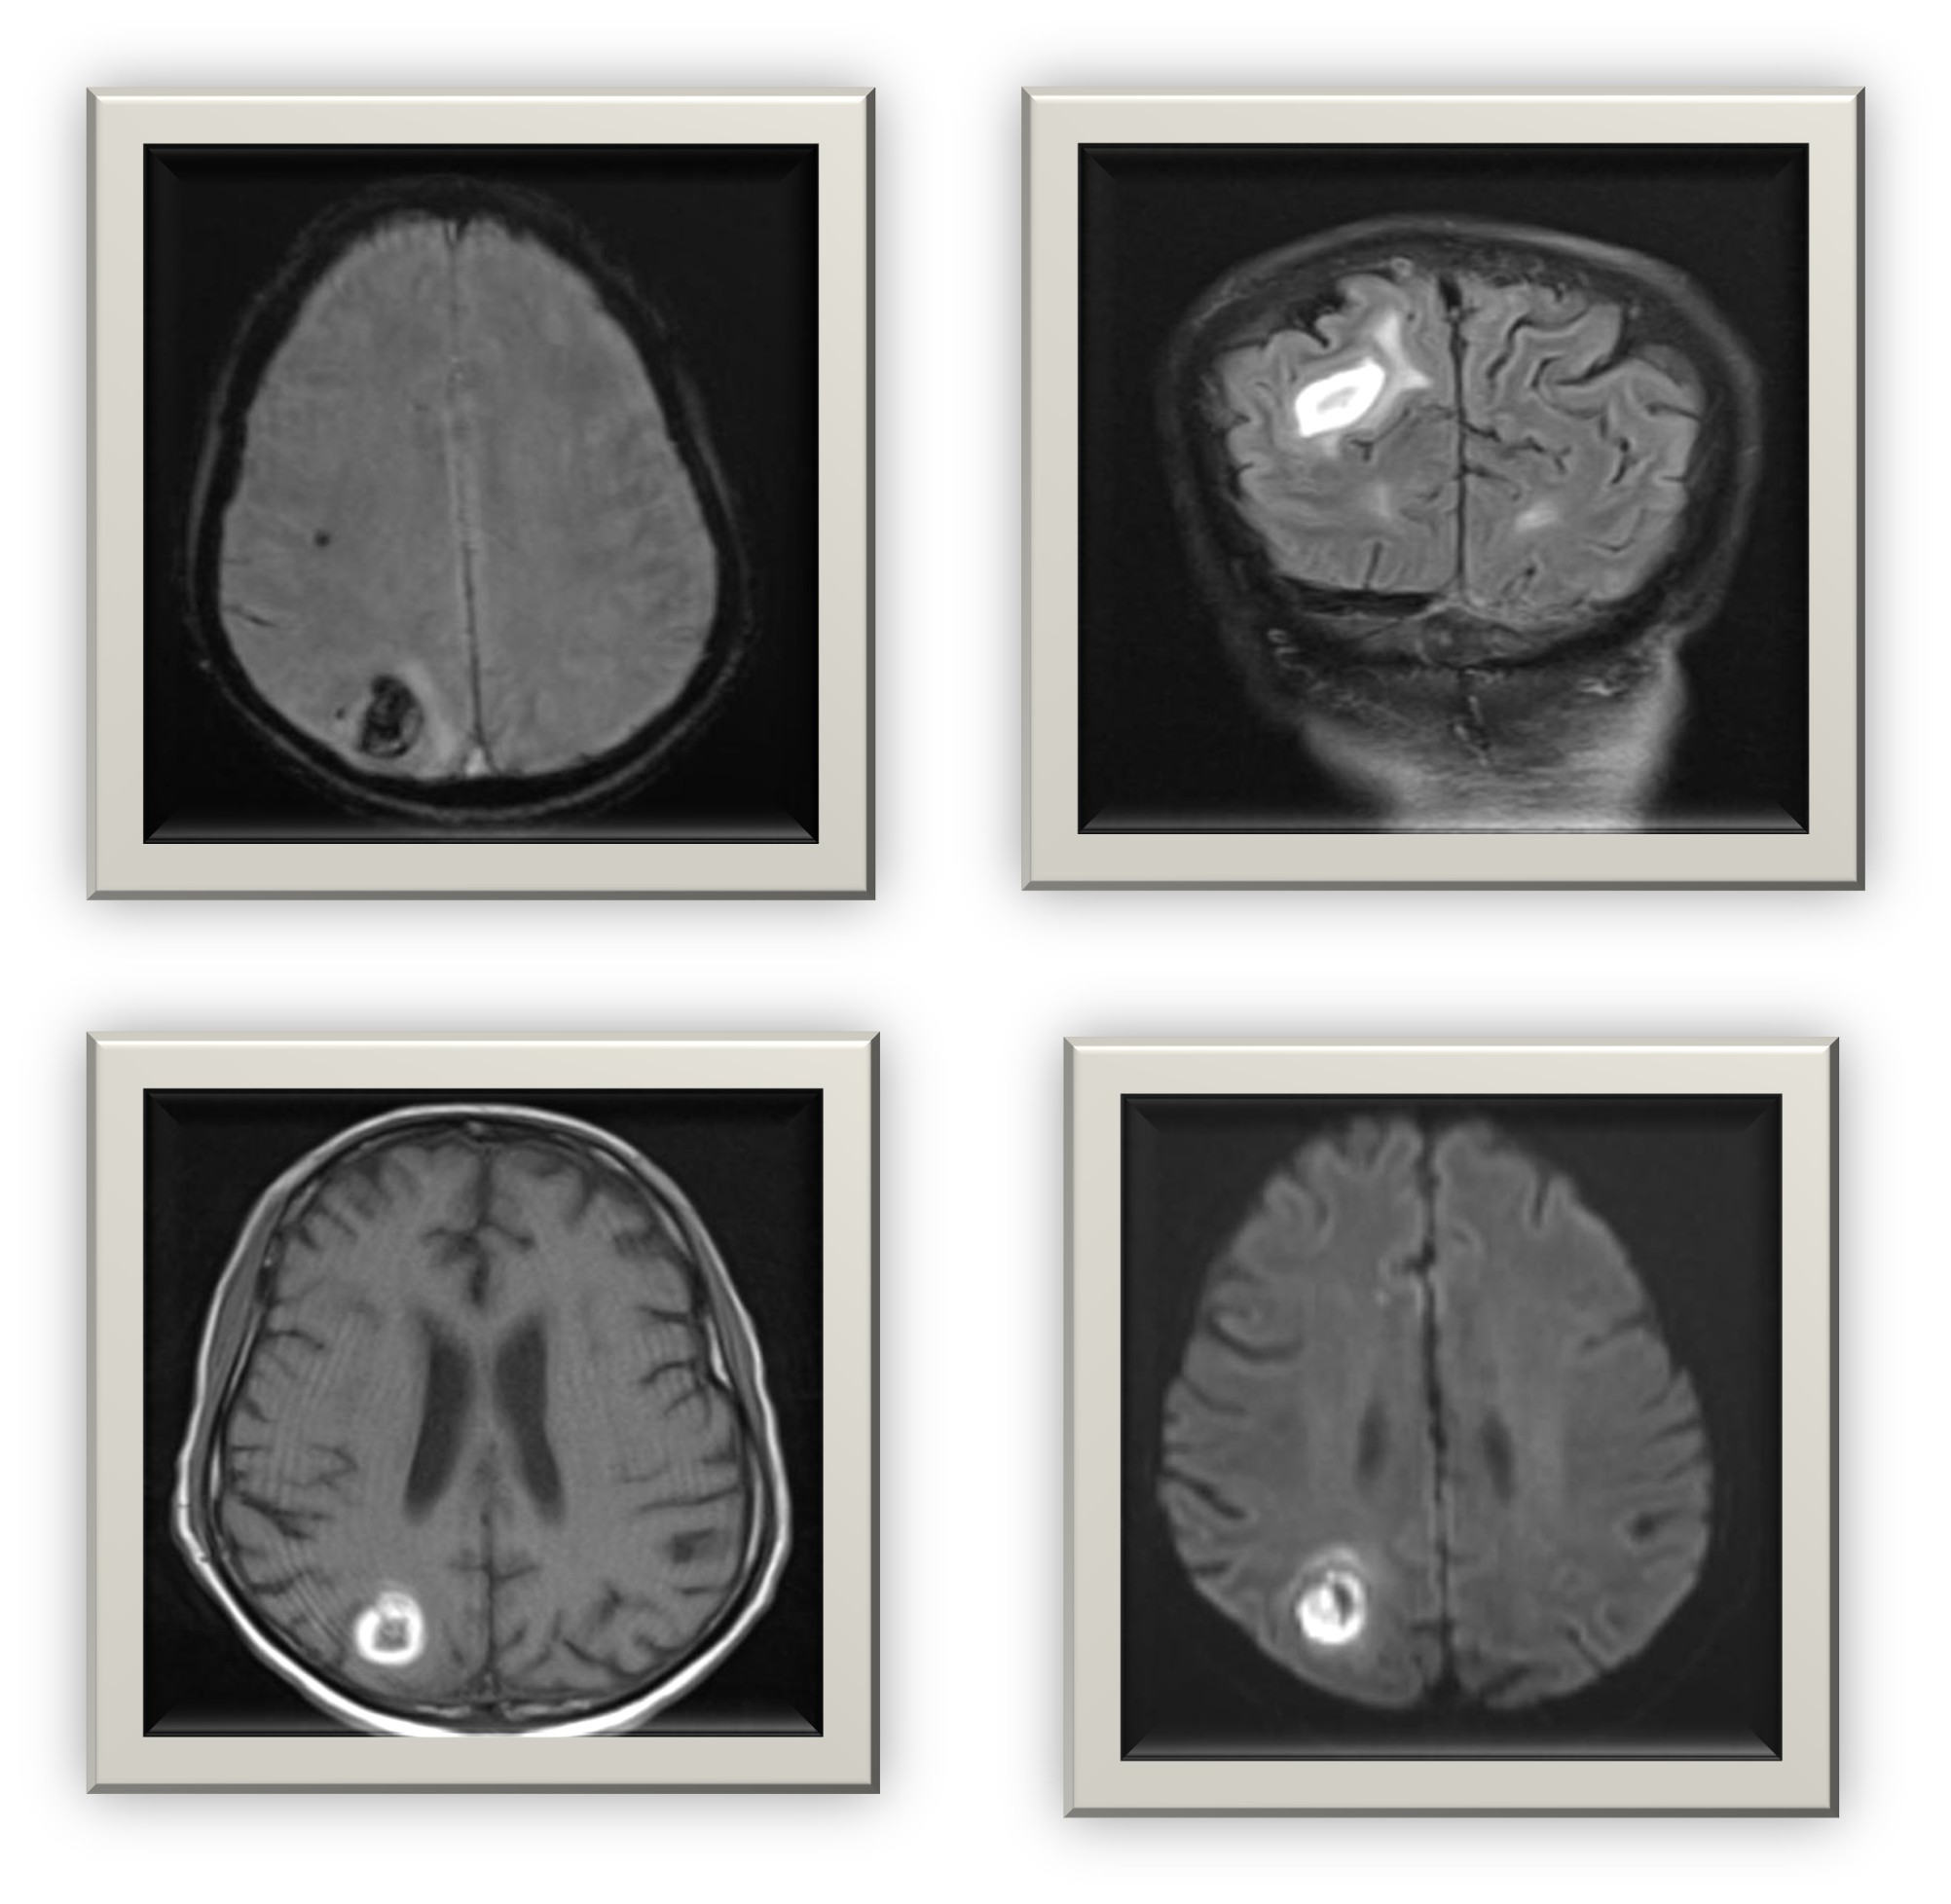

MRI Brain: Ring-enhancing lesion in the right frontoparietal region with surrounding edema consistent with cerebral abscess or meningoencephalitis.

The negative cultures and serologies created diagnostic uncertainty. Imaging played a pivotal role in guiding diagnosis. MRI findings showing ring-enhancing lesions in both spine and brain raised suspicion of disseminated bacterial infection or neurotuberculosis. However, the acute presentation and neutrophilic response favoured a pyogenic etiology.

Neurological manifestations emerged later, emphasizing how systemic infections can evolve to involve the CNS. The ring-enhancing lesion seen on MRI, along with clinical response to antibiotics, confirmed an infective meningoencephalitis component.

Imaging correlation (especially MRI) is invaluable when systemic infections involve the CNS or spine.